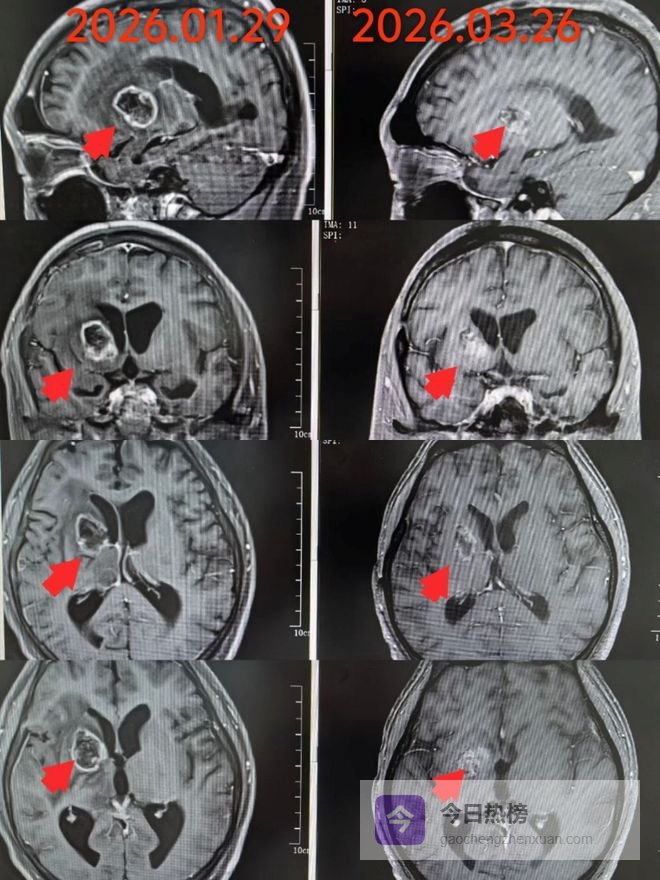

影像学改善: 复查颅脑MR显示,病灶及周围水肿得到明显改善,病情得到有效控制。

杨洋主任在查房后,第一时间指着电脑屏幕上的影像,细致地为家属讲解治疗前后的变化。那些微小的改善,在医生眼中是治疗的成果,在家属心中则是重生的希望。